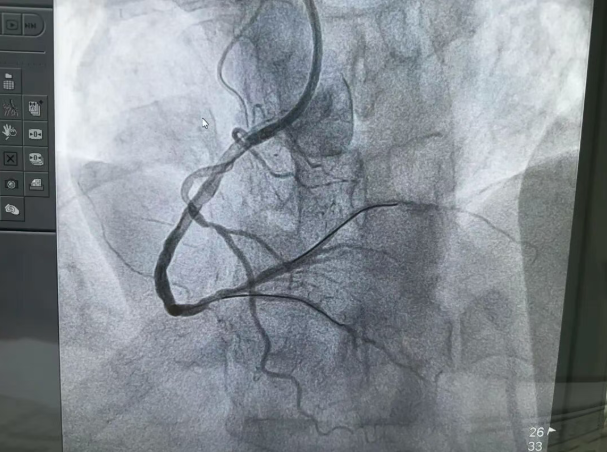

▲术后